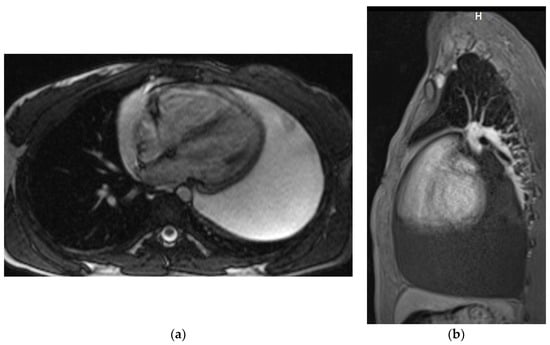

Chest MRI

Magnetic resonance examinations of the chest were performed by Siemens Avanto 1.5T scanner (Siemens, Munich, Germany). Routine MR sequences and ECG-gated sequences were used and T1-weighted and T2-weighted and fat saturation images were acquired. The examination was performed with gadolinium contrast agent administered through a double syringe system Optistar SF (Optistar, San Francisco, CA, USA) (Figure 3a,b).

Figure 3. Chest MRI. T2-weighted image, axial view (a) T1 weighted image with fat saturation and with contrast enhancement, sagittal view (b). Large pericardial effusion is seen, hyperintense on T2-weighted image (a) and hypointense on a T1-weighted image (b).